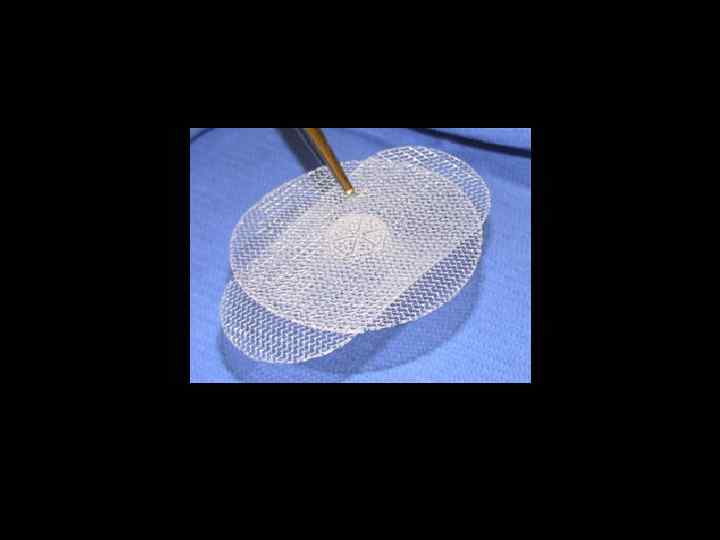

ПЛАСТИКА ГРЫЖЕВЫХ ВОРОТ • Местными тканями • Трансплантат "Секрет радикального грыжесечения будет найден лишь тогда, когда появится возможность производства искусственной ткани, столь же прочной, как фасции и сухожилия". Т. Биллрот, 1871 г.

ВАРИАНТЫ ФИКСАЦИИ ТРАНСПЛАНТАТОВ • sublay • inlay • onlay